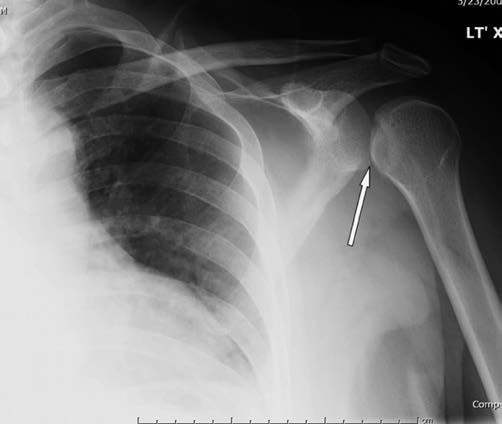

1. What is this case, ?

a. Clavicle fractures (A) are often described by location, with the clavicle divided into thirds: proximal, middle, or distal. Note the scapular fracture (B) as well.

b. Clavicle fissure (A) are often described by location, with the clavicle divided into thirds: medial, middle, or distal. Note the scapular dislocation (B) as well.

c. Clavicle fracture complete (A) are often described by location, with the clavicle divided into thirds: medial, middle, or distal. Note the scapular fracture (B) as well.

d. Clavicle fracture (A) are often described by location, with the clavicle divided into thirds: medial, middle, or distal. Note the scapular subluxaxion (B) as well.